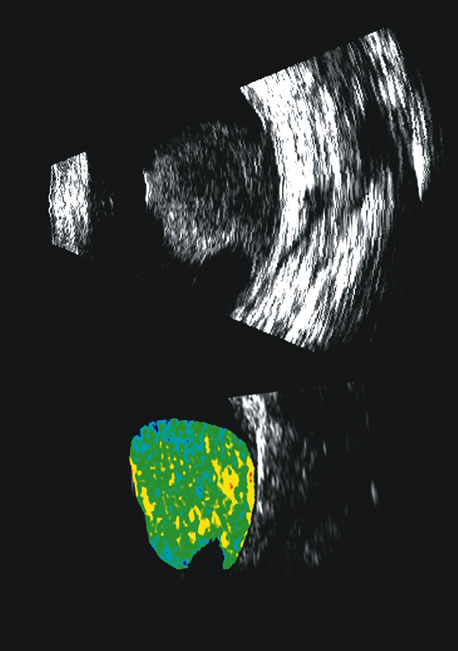

| The use of three-dimensional data acquisition along with surface

and volume rendering of three-dimensional ultrasound data is becoming

more commonplace in medical ultrasonography,37 particularly in obstetrics and gynecologic applications.38–40 In ophthalmology, instrumentation that digitizes radial B-scans

is commercially available.41,42 In addition, tissue volume measurements made from delineation of tissue

boundaries in serial scans have been shown to have an accuracy of ±2% in vitro.43 Such measurements must be corrected for the anamorphism inherent in B-scan

images, where anterior-to-posterior scale is

related to the speed of sound and lateral scaling is related to transducer

angle or displacement. Comparison of in vivo volume determinations of ocular tumors made with this method and volumes

computed from ultrasonically determined tumor linear dimensions using

an ellipsoidal solid formula44 showed the latter to be of variable accuracy, sometimes producing errors

of up to 50%. The representation of volume and three-dimensional perspectives of the diseased vitreous, retinal detachment, choroidal detachment, and tumors can add to presurgical conceptualization and is critical to characterization of tumors in relation to prediction of lethality.45 In addition, volume measurement of the choroid permits studies of both surgical and physiologic rates of clearance of hemorrhage, whereas vitreous volume studies can make the estimation of gas or other vitreous substitutes for replacement more accurate (Fig. 25). Spectral parameter imaging, a digital signal processing technique that examines the frequency content of backscattered ultrasound signals, has been shown to be predictive of increased lethality in certain patients and also to be useful in the in-vivo identification of high-risk melanomas for treatment staging.46–48 The shape, density, orientation, and number of scattering elements in a region influence not only the relative amplitude or brightness of a pixel on B-scan but the frequency content of the signal returned to the transducer.19 The concept of differentiating tissue backscatter in a quantitative manner rather than in simple qualitative descriptions of hypo-, iso-, and hyperechoic variations in gray scale allows for maximum use of information available in the digital ultrasonograms. These techniques can be extended to examining the functional anatomy of the eye as well as disease states other than solid tumors (Fig. 26). Improved transducer fabrication technology can now produce clinically useful broadband 20 MHz transducers. This allows for biometry of the posterior coats with an accuracy and precision previously unachievable. In addition to resolving retinal layers and choroid typically seen with optical coherence tomograpy, ultrasound at 20 MHz still provides depth of penetration through pigmented lesions and beyond the posterior scleral boundary. Differentiation of underlying retinal disease can thus be improved, even in the presence of media degradation that causes light scattering or even in the case of frank opacities. |